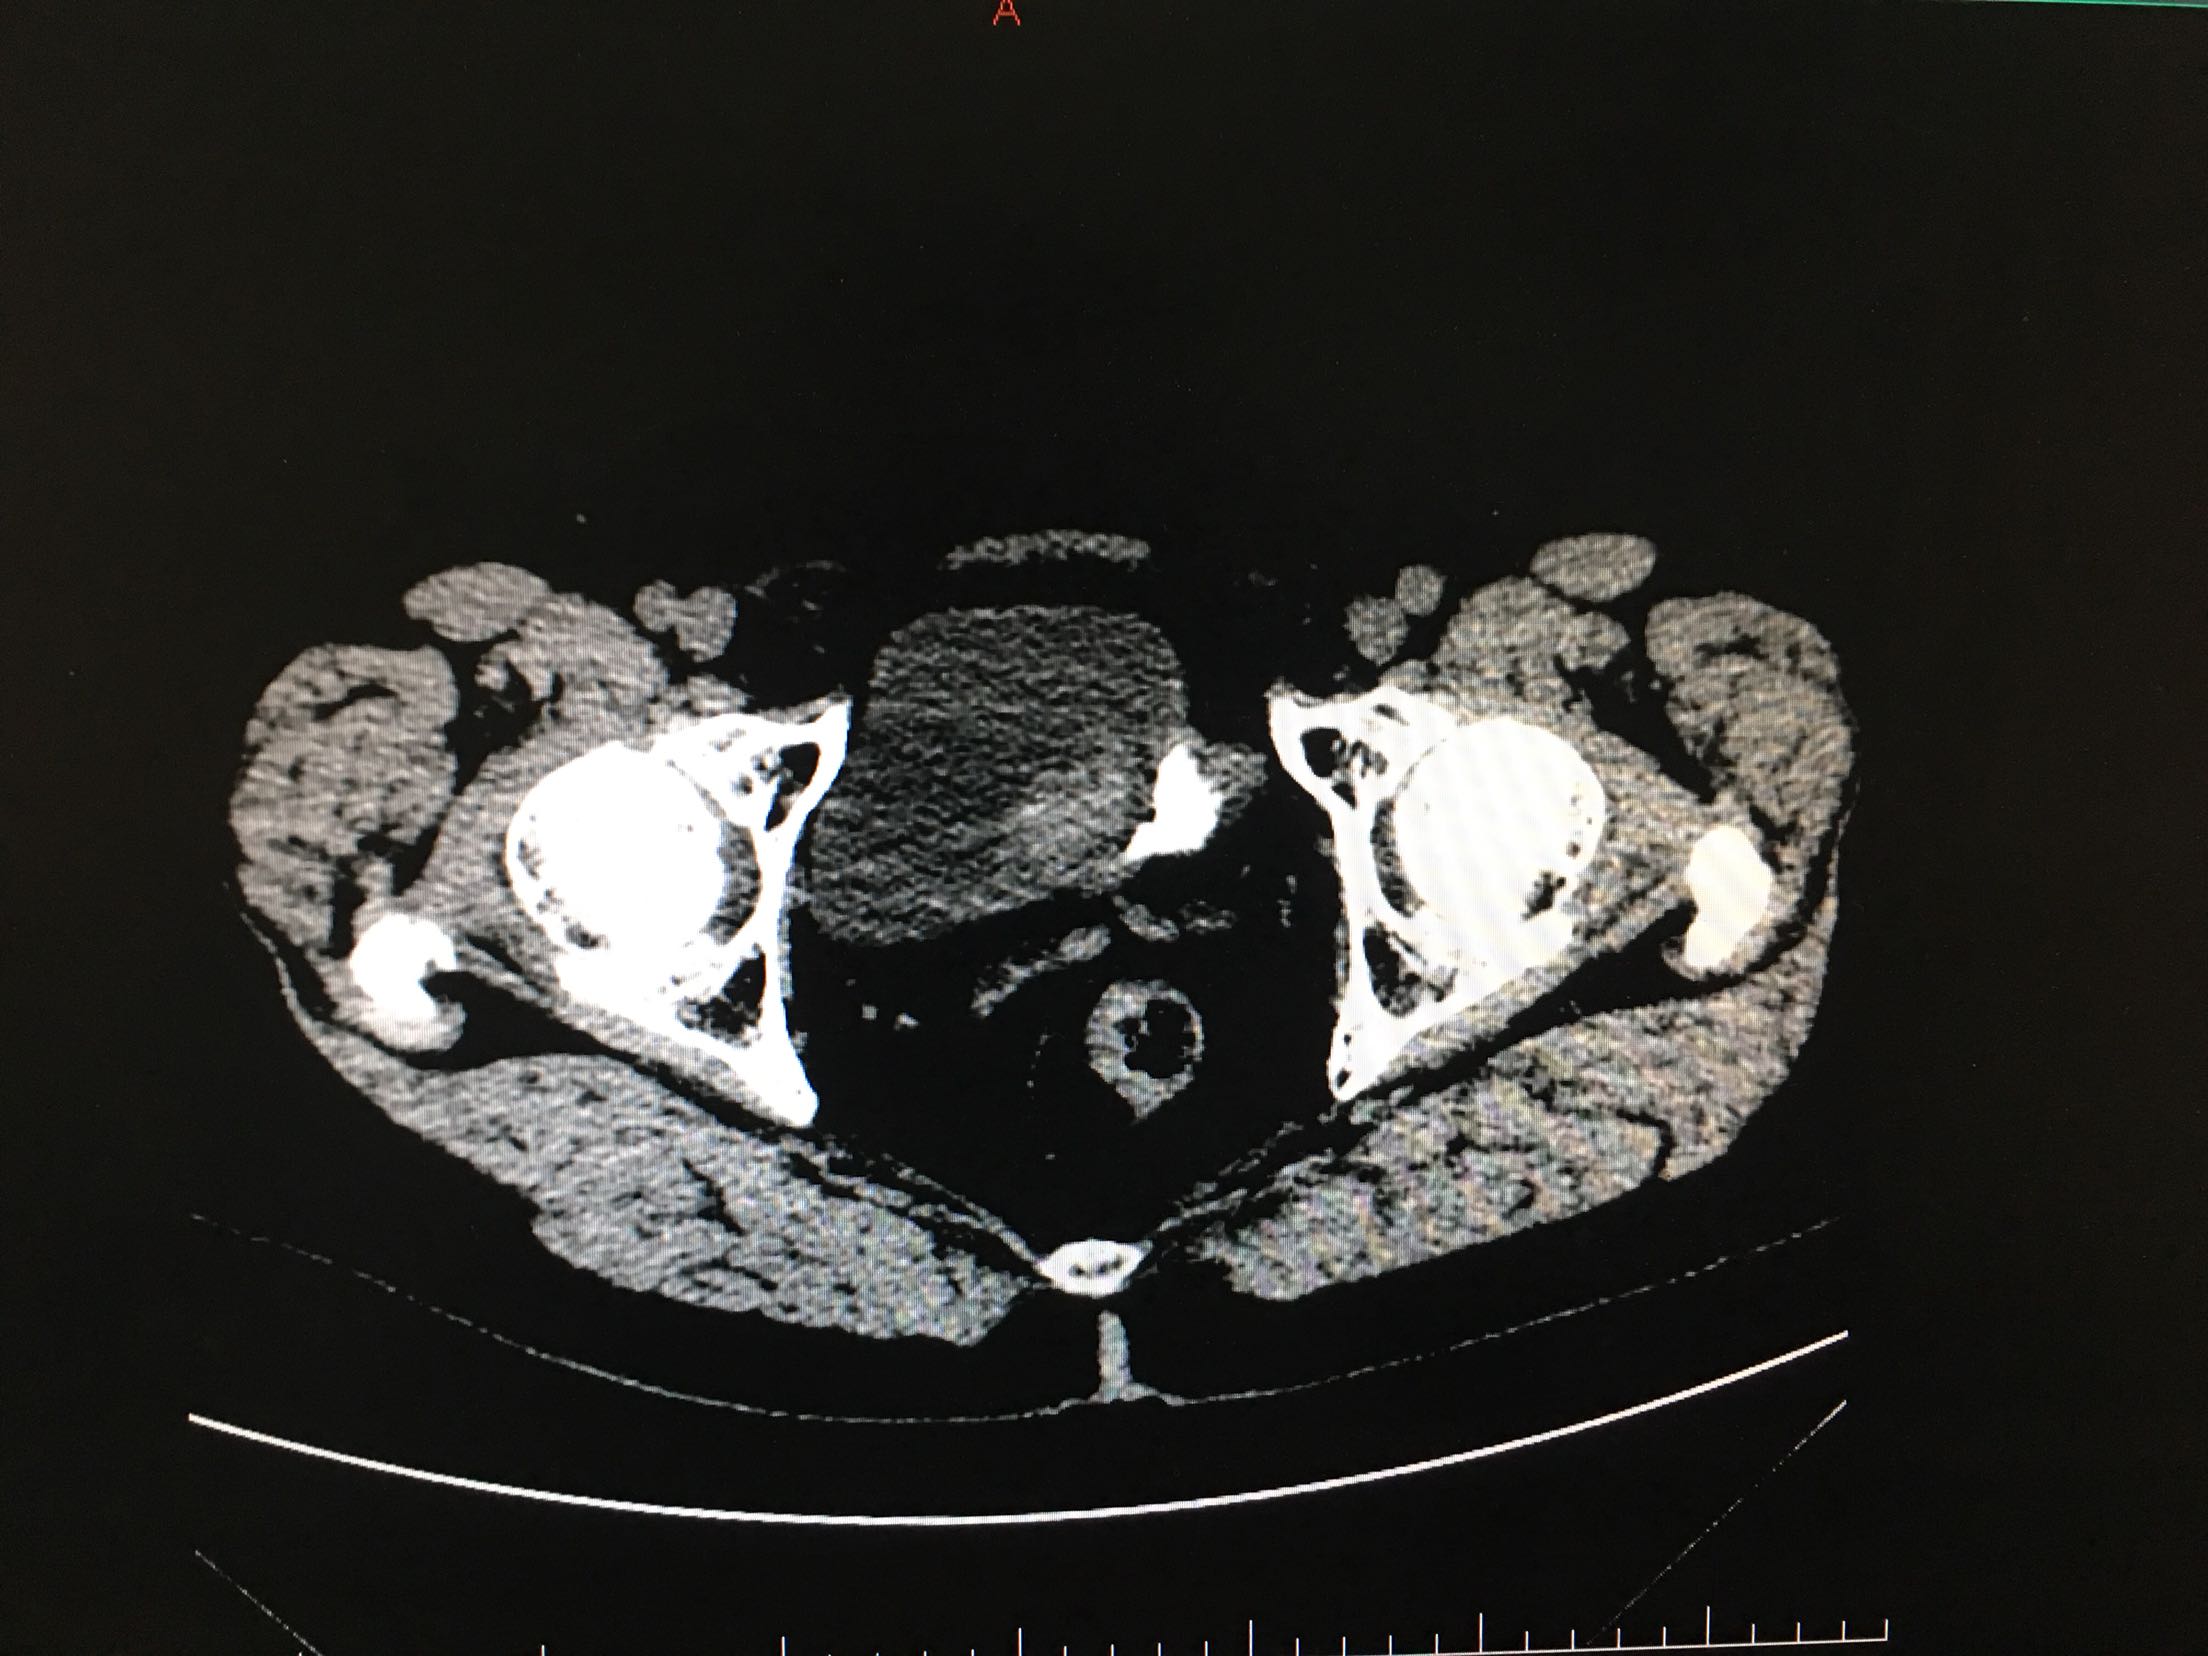

67岁男患者 2年前患者因为尿潴留检查发现前列腺癌,行经尿道前列腺癌电切改善排尿,术后给予内分泌治疗,5天前患者出现肉眼血尿,尿频、尿急、尿痛症状严重。患者为求进一步诊治来我院。患者发病以来精神状态差,体重减轻。

查体:双肾区无叩击痛,双输尿管走形区无压痛,耻骨上压痛,叩诊未见明确浊音。 辅助检查:ctu:膀胱占位性病变及直肠壁增厚,结合病史考虑前列腺癌伴膀胱及直肠受累。 psa:35ng/ml。